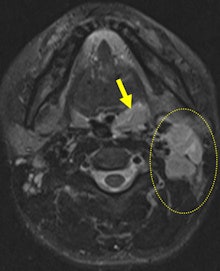

On MRI, oropharyngeal tularemia mostly presents with unilateral lymphadenopathy and associated oropharyngeal lymphoid tissue hypertrophy. A spectrum of homogeneous to inhomogeneous, and/or peripheral enhancement is parallel to development of central necrosis in the lymph nodes. Accompanying increased signal intensity occurs on T2-weighted images, and contrast enhancement of neighboring soft-tissue planes may be noted, especially in cases of suppuration. Restricted diffusion and an apparent diffusion coefficient (ADC) ranging from 0.5-1.05 mm/sn2 also are evident.

The main weakness of MRI is that its findings are nonspecific. Furthermore, both conventional MRI and diffusion-weighted imaging findings (ADC values) overlap with other granulomatous infections such as cat scratch disease and some malignant neoplasms such as squamous cell carcinoma, the researchers found.

Oropharyngeal tularemia should be considered in patients with a sore throat -- with or without an accompanying tender head and neck mass -- that does not respond to beta-lactam antibiotics and demonstrates necrotic lymphadenopathy and/or oropharyngeal lymphoid tissue hypertrophy with restricted diffusion in an MRI examination, particularly in endemic areas, they concluded.